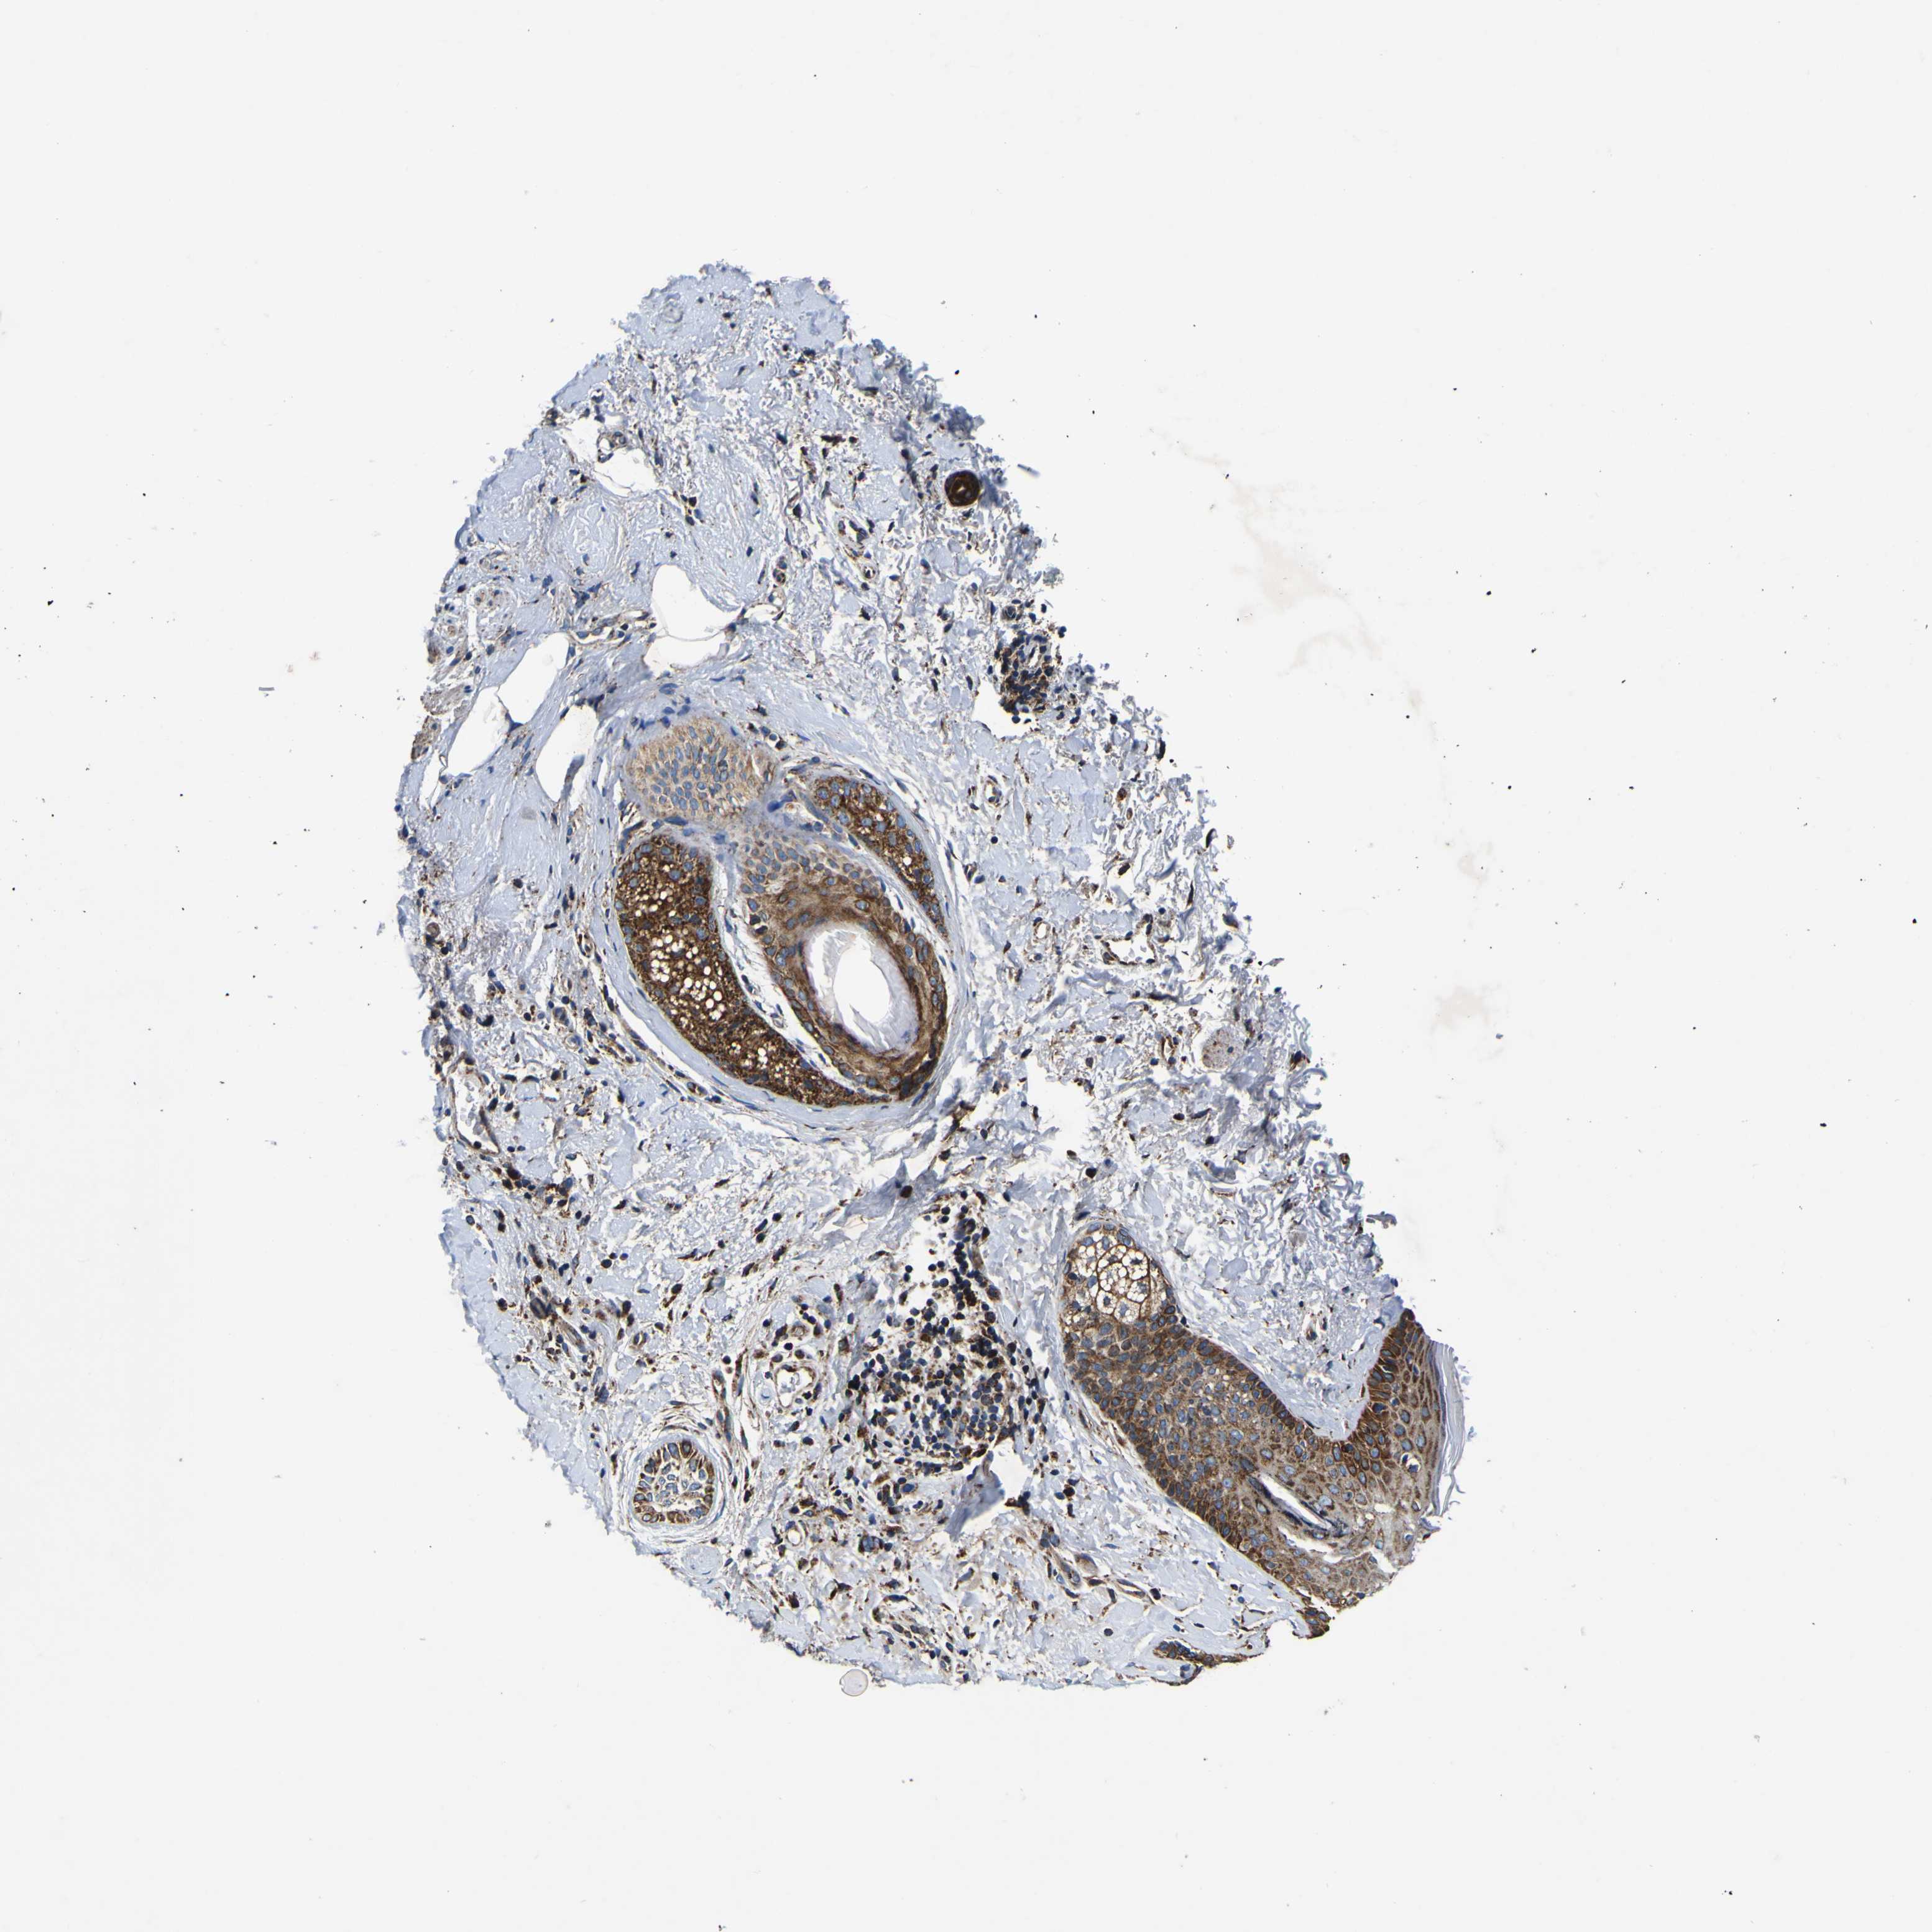

CANCER SKIN CANCER Show tissue menu

Basal cell and squamous cell cancer

SKIN CANCER - Protein expressioni

A mouse-over function shows sample information and annotation data. Click on an image to view it in a full screen mode. Samples can be filtered based on level of antibody staining by selecting one or several of the following categories: high, medium, low and not detected. The assay and annotation is described here.

Each image is clickable and will lead to virtual microscopy that enables deeper exploration of all samples and also displays staining intensity scores, fraction scores and subcellular localization as well as patient and tissue information for each sample.

Antibody HPA012897

Staining

High

Medium

Low

Not detected

Intensity

Strong

Moderate

Weak

Negative

Quantity

>75%

75%-25%

<25%

None

Location

Nuclear

Cytoplasmic/membranous

Cytoplasmic/membranous,nuclear

Squamous cell carcinoma, NOS

Basal cell carcinoma